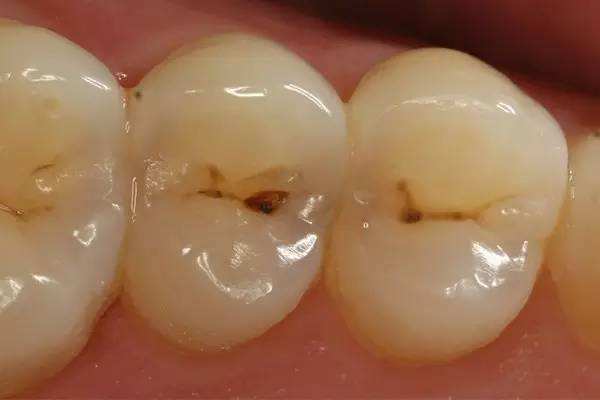

浅龋

也就是刚开始蛀牙的时候,牙齿表面会呈现黑黑的形状,但是不会感觉到酸或者疼,这个时期是特别容易修复的,只需要清理完黑色物质用材料把缺失部分补好就好了。